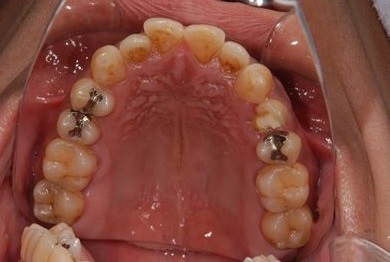

セラミック治療+歯肉歯槽骨整形術

| 性別/年齢 | 男性 / 45歳 | ||||||||||||||||||||||||||||||||

| 主訴 | 詰め物をしている歯が割れてしまったので、治療して欲しい。 | ||||||||||||||||||||||||||||||||

| 治療方針 | セラミック治療にて、審美的回復を行う。 | ||||||||||||||||||||||||||||||||

| 治療内容 | メタルボンドセラミッククラウン1本(メタルボンドセラミック用土台1本)、歯肉歯槽骨整形手術 | ||||||||||||||||||||||||||||||||

| 総治療費 | 157,185円 | ||||||||||||||||||||||||||||||||

| 治療期間 | 7ヶ月 |